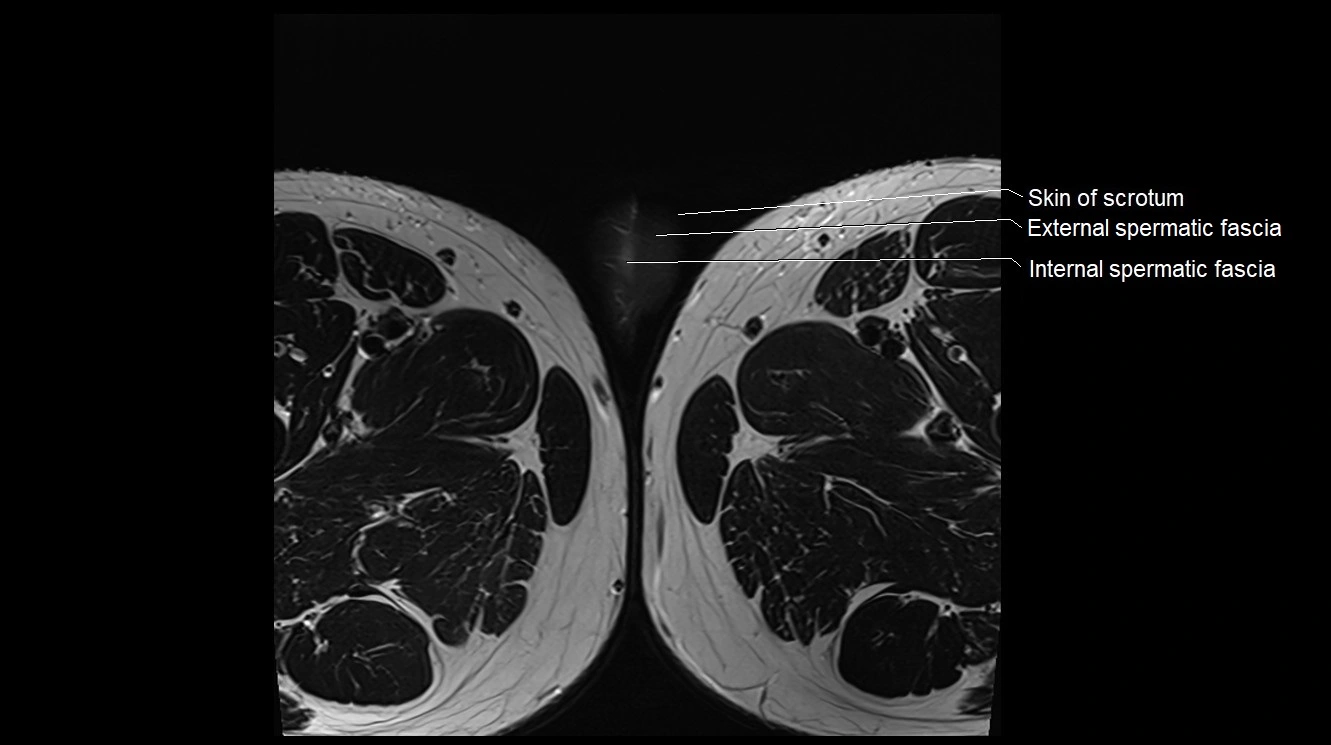

MRI image